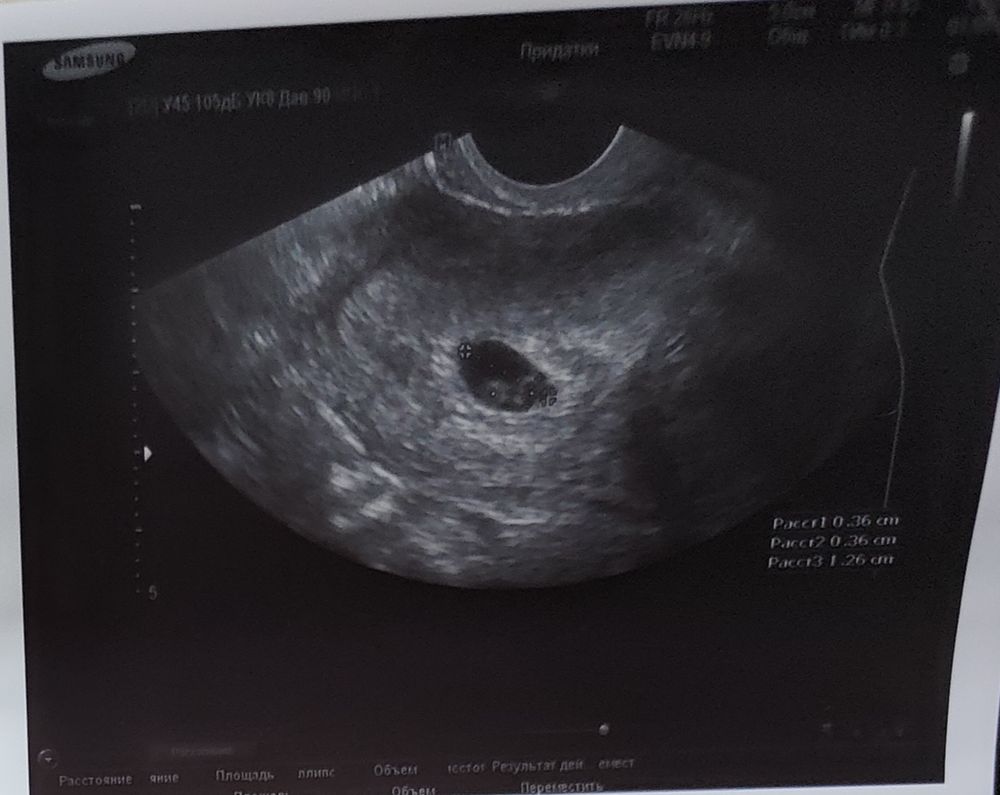

УЗИ на 23 дпп (5,2 нед):

1 плодное яйцо. 2 [хориона](?). 2 эмбриона.

Нютусь, увидела сейчас описание врача к фото. Я тоже в замешательстве 🤨

Если идти от обратного. Эмбрионы то не слились, уже хорошо, у каждого ктр 1,8. Сидят каждый в своём колесике диаметром 3,6.

Это или моно ди, или вообще ди ди